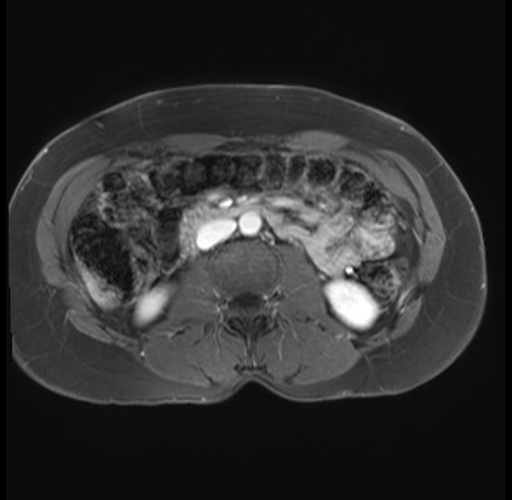

Imaging Analysis

Look through the patient's CT scan to identify any areas of concern for the necessary procedure.

Based on your CT findings, which issue(s) are present and would give reason for "planned slowing down moment(s)" in this case?

Considering a standard distal pancreatectomy procedure, what step(s) of the operation would you do differently in this case?